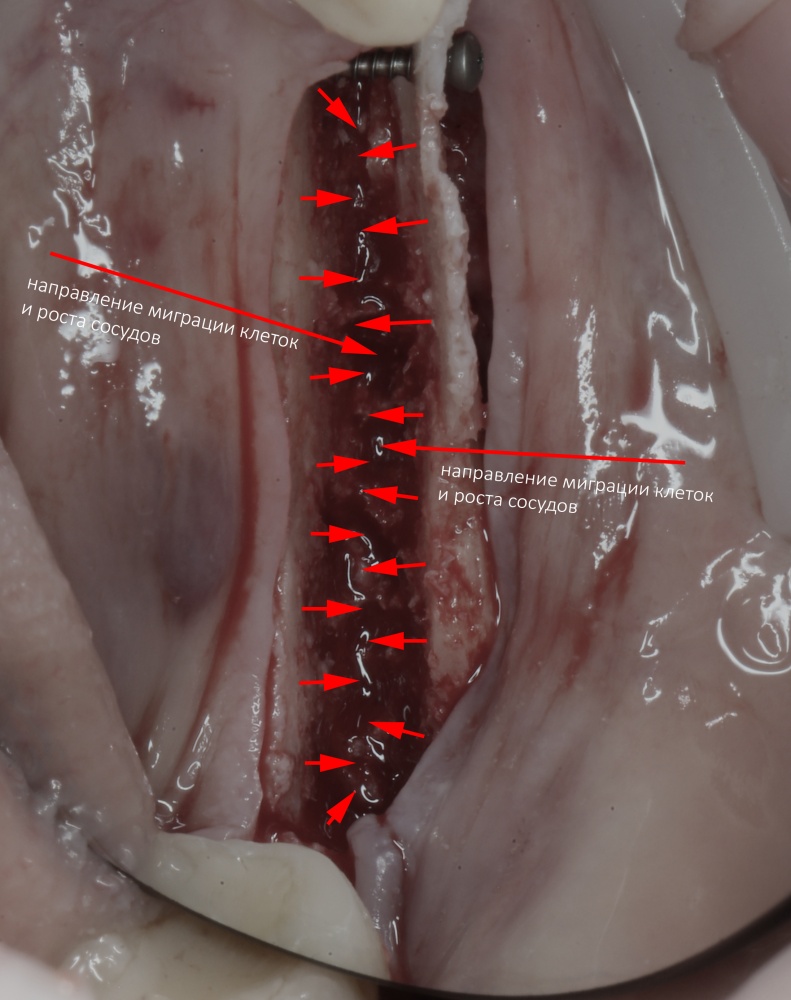

Во-вторых, мы, фактически, сразу создаём идеальные условия для регенерации костной ткани — наш костный дефект со всех сторон окружён раневой поверхностью, а это значит, что миграция клеток и рост будут идти со всех сторон (см. «Предел роста»). Это чем-то похоже на синуслифтинг, неудачи в котором крайне редки:

В-третьих, достаточно большая раневая поверхность «привлекает» большее количество макрофагов, следовательно, мы имеем больше БКМ, факторов роста, управляющих регенерацией кости. Уточню — без добавления аутокостной стружки или чего-то там искусственного: